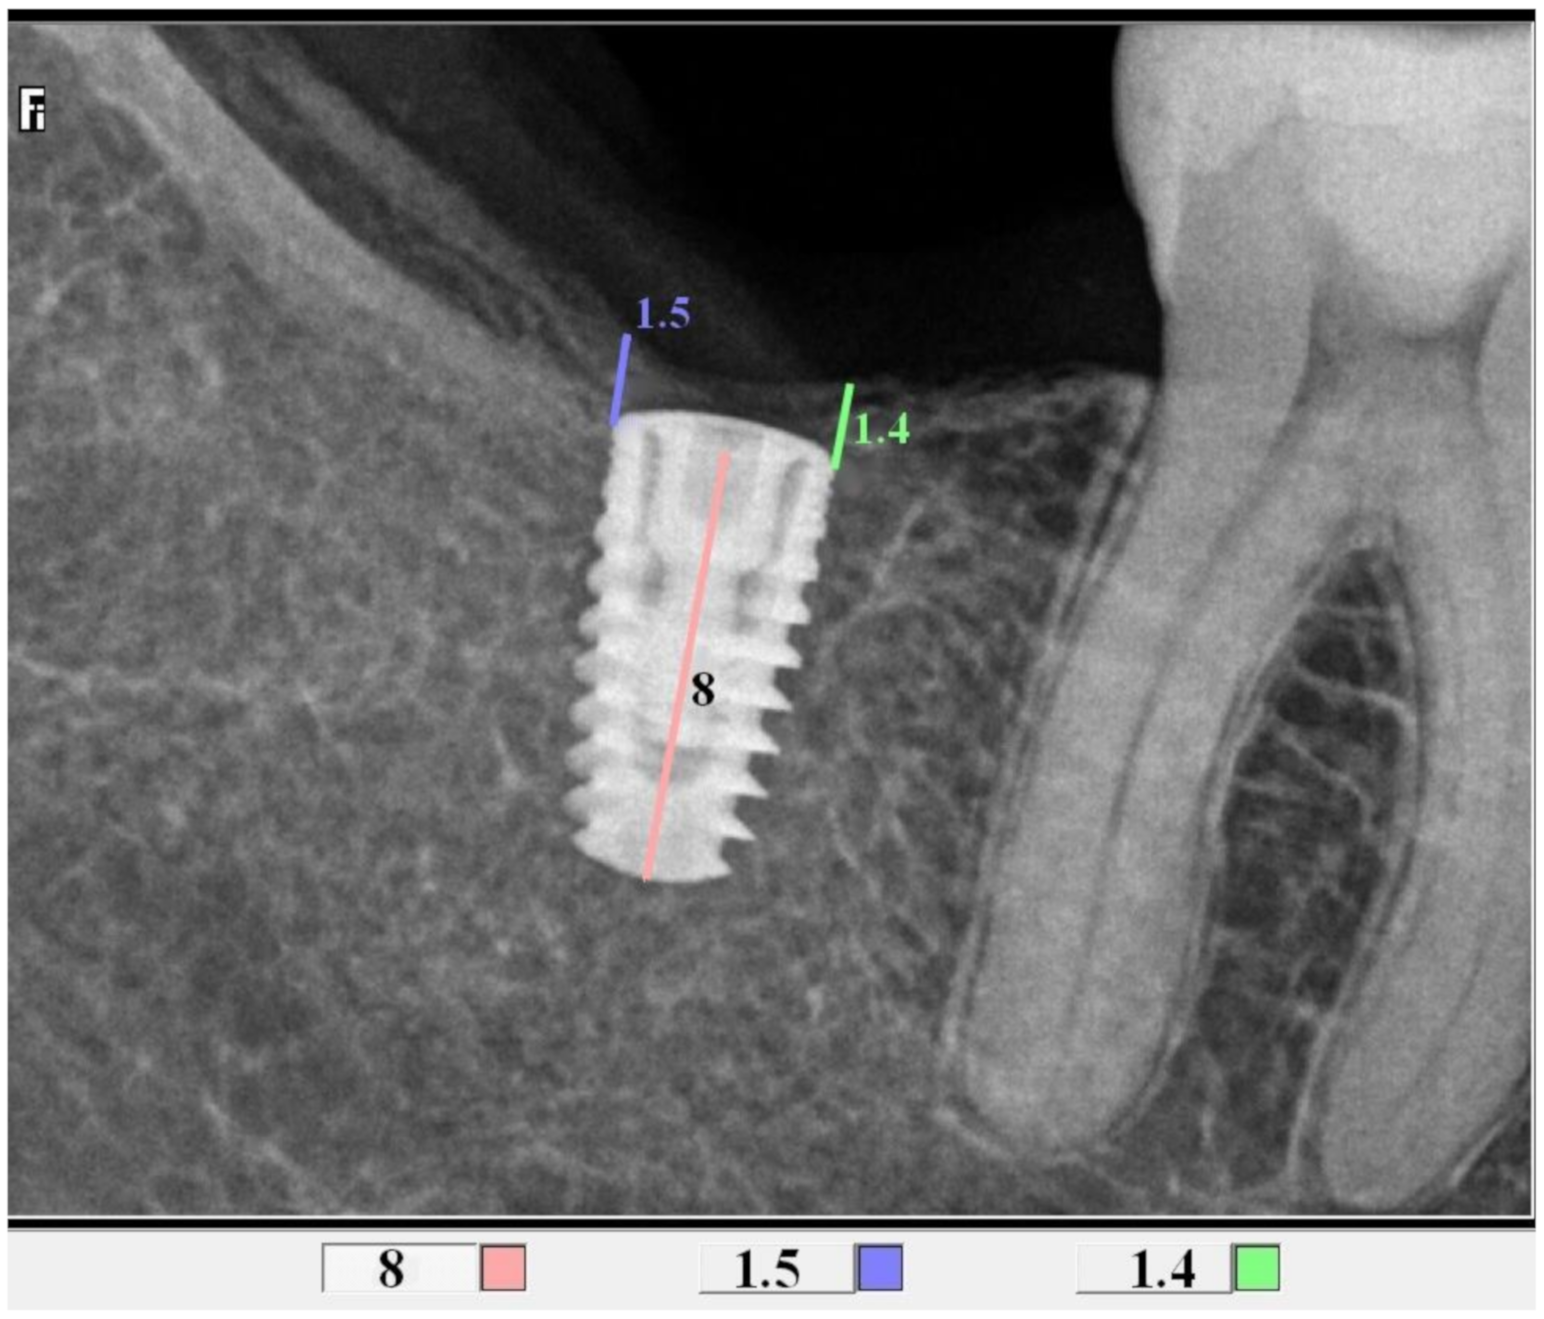

All control tests were performed by the second operator (GT). The evaluation of bone loss/growth was performed on the basis of radiovisiography (RVG) images taken with the long cone paralleling technique using a positioner (Figure 1). The bone level in the immediate proximity of the implant was determined using the RVG image analysis. Three targeted radiographic images were compared on the day of implantation, and after six and twelve weeks. Bone tissue loss or growth were assessed using software designed for analyzing digital radiovisiography. The calculated value was the arithmetical mean of the measurements performed on both sides of the implant that were visible in the two-dimensional image (the calculations were made starting at the head of the closing screw). To enable effective calibration, a measurement was made along the long axis of the implant (a) (Figure 2, Figure 3 and Figure 4), which was related to its actual length (y) and was calculated from Formula (1) as follows:

Figure 3.

Measurements of bone growth in the proximity of the implant (DIS, dental image software).